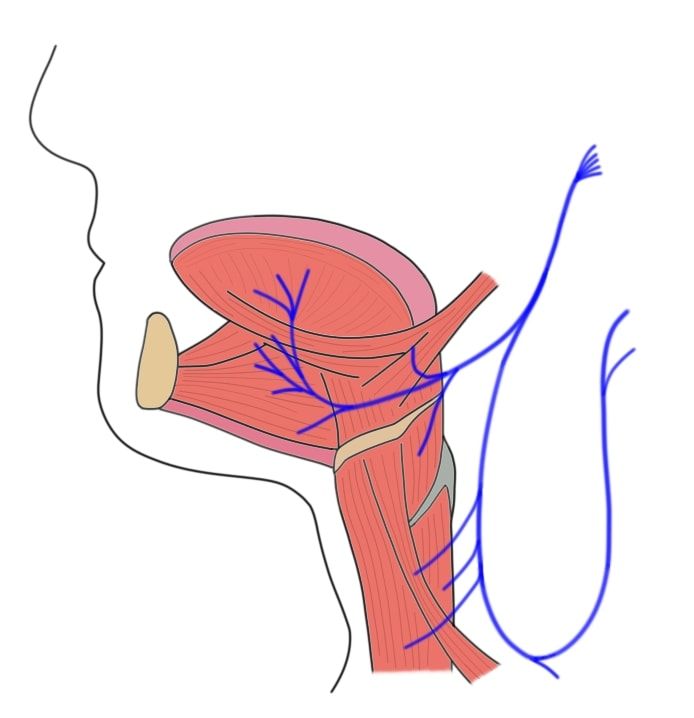

label the image of the hypoglossal nerve.

The Hypoglossal Nerve (CN XII) – Course – Motor – TeachMeAnatomy

Neuroanatomy, Cranial Nerve 12 (Hypoglossal) – StatPearls – NCBI Bookshelf

Hypoglossal Nerve Intermedullary Course

Hypoglossal Nerve Intermedullary Course

Hypoglossal Nerve (XII) and Canal

Hypoglossal Nerve (XII)

The Wonders of the Tongue — Its Muscles with Motor and Sensory Nerve …

The Tongue – Muscles – Innervation – Vasculature – TeachMeAnatomy